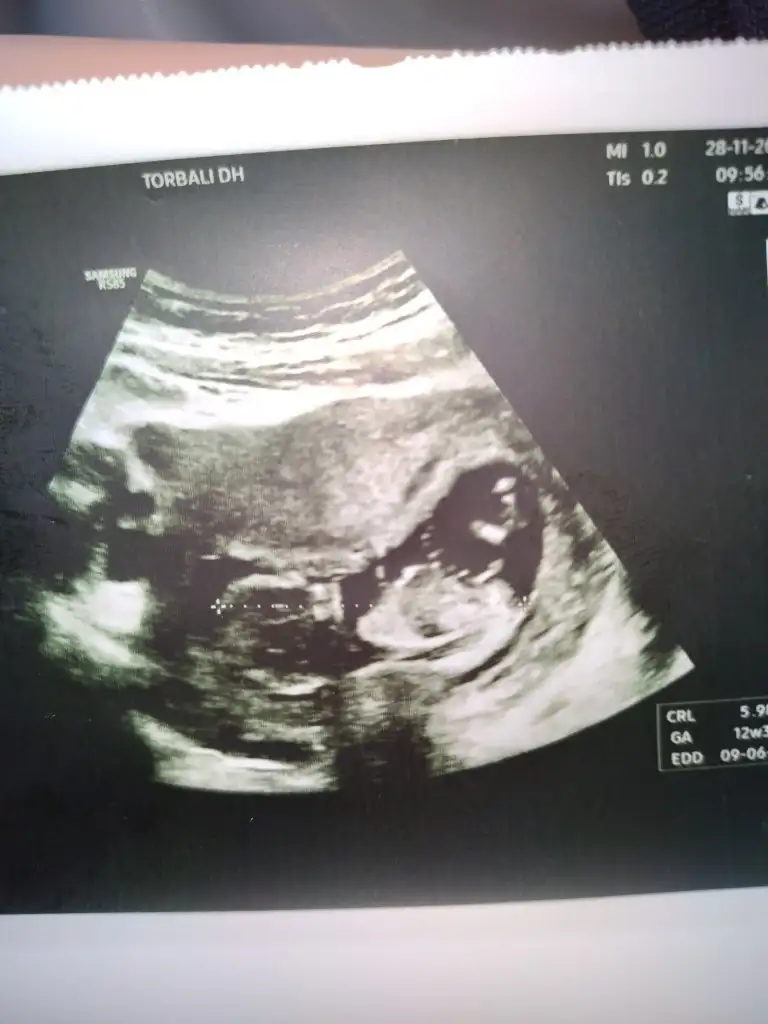

Merhabalar 12 haftalık bebeğim cinsiyet tahmini yapan varmı acaba

Eklentiler

• IMG_20221128_104000.webp

25 KB · Görüntüleme: 301